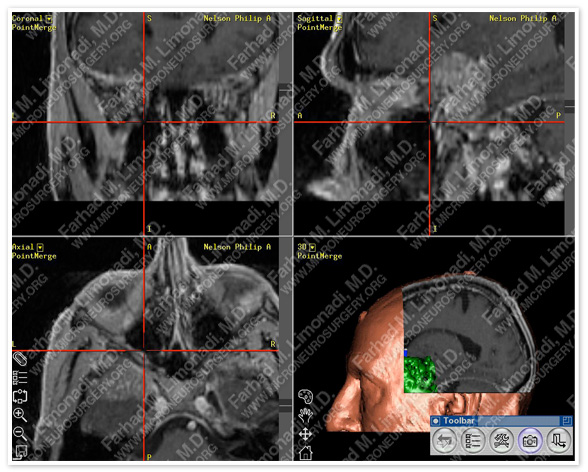

Post-op Imaging

Before Operation                                                    After Operation

Post-op MRI shows complete resection of the tumor with no injury to surrounding neurovascular structures.